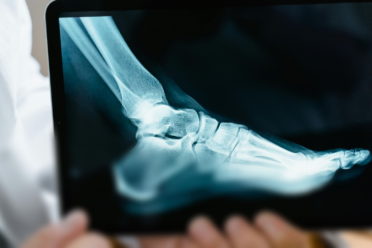

Czy kontuzja Roberta Lewandowskiego da się wyleczyć przed EURO? Kontuzje mięśniowe – naciągnięcia, naderwania i zerwania